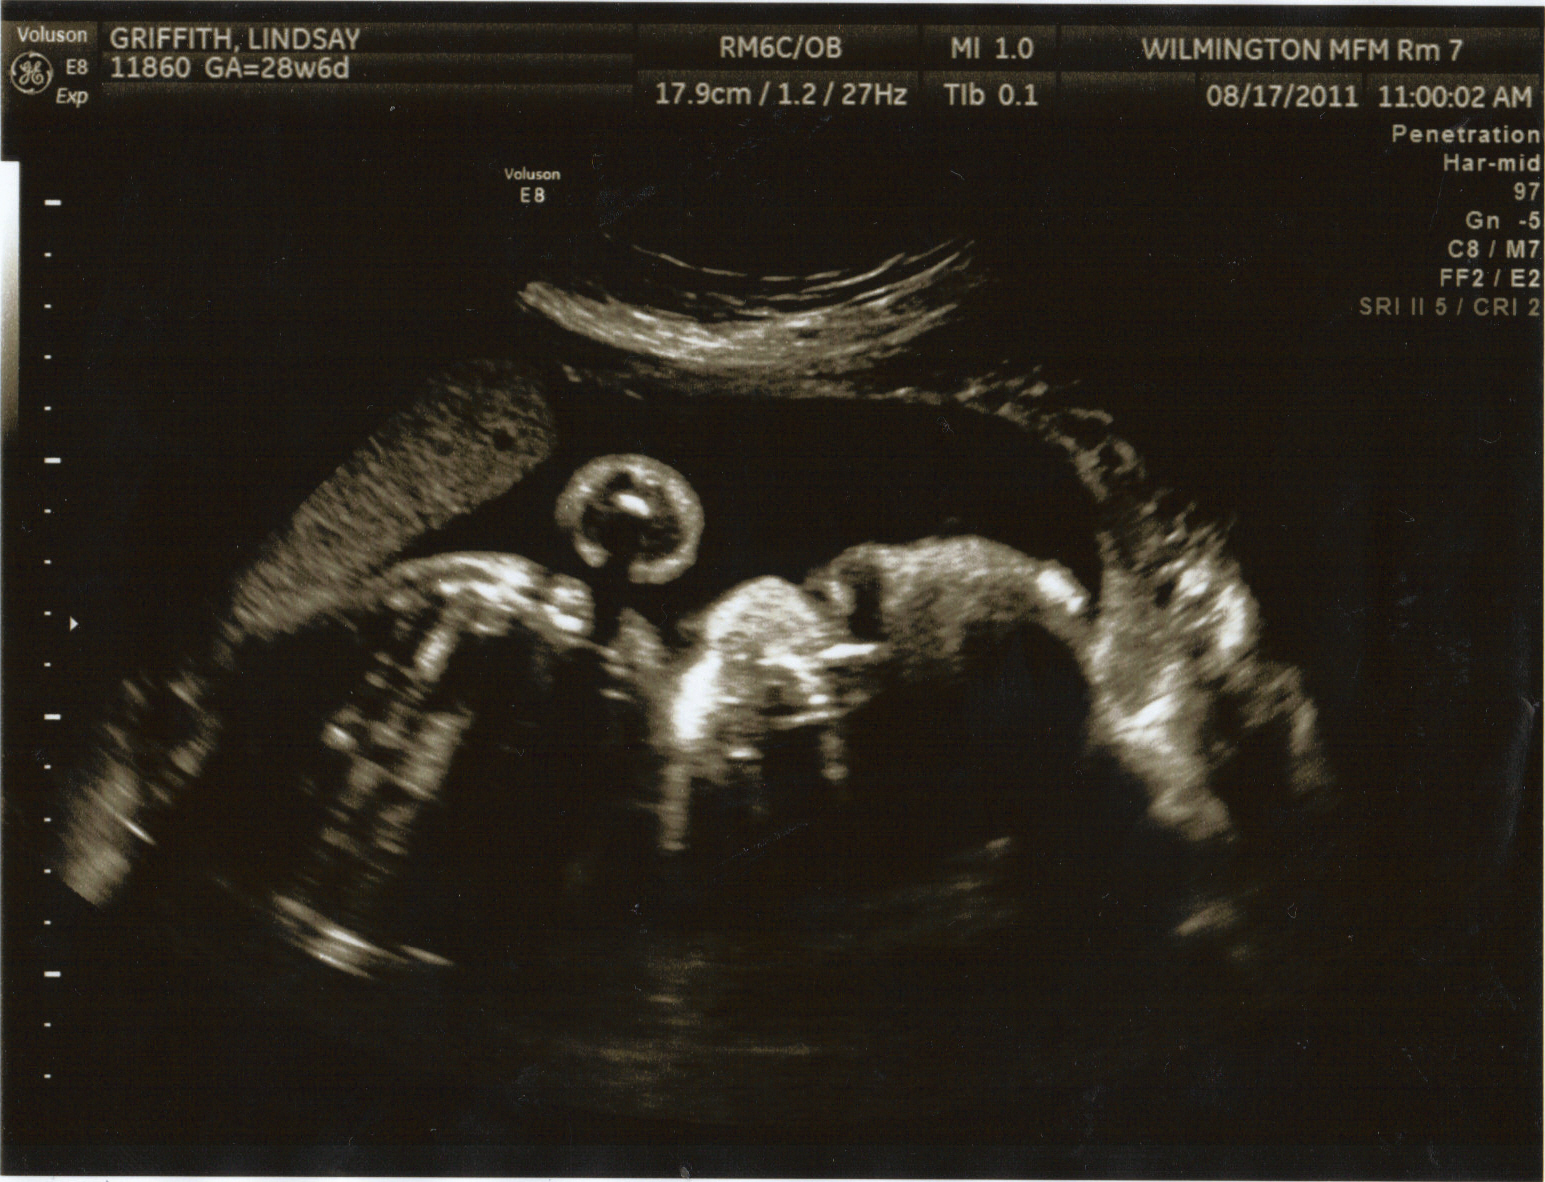

Growing Baby G! 28 Week and 6 Days ultrasound